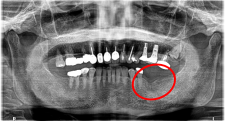

上下、歯がないところに入れ歯を作ったが、使っていない。インプラント治療をしてほしい。

上顎4本残っている歯を抜歯し、インプラントを6本埋入。下顎、右下2本、左下1本埋入。

所感

上顎3本は、もし義歯で対応する場合であれば、保存してマグネット義歯の支台として活用します。しかし、患者さんが義歯ではなくインプラント治療を希望され、かつ、見た目が自然でよく嚙めるようになることが最優先事項でしたので、相談したうえで3本の歯は積極的に抜歯しました。

治療後、「インプラント治療に満足しています。食事が楽しくなりました。スタッフの方の説明がわかりやすかったです。1年間ありがとうございました。」と、とてもうれしくなる感想を書いていただきました。

上顎:全額治療 ¥3,280,000(税込)

下顎:インプラント3本 ¥363,000×3本=¥1,089,000(税込)

合計:¥4,369,000(税込)

Before

After